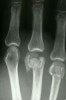

X-ray : metacarpal head fracture

드물고, 보통 축성 압박력이나 전단력, 또는 직접 외상에 의하여 발생하는 관절내 골절입니다.

제 2수지에서 가장 흔하게 발생합니다.

반드시 oblique 사진을 함께 찍어 관찰하여야 하며, 필요하면 투시 영상 장치하에서 관찰하거나 CT를 시행해서라도 골절 여부를 확인하여야 합니다.

전위가 없으면 보존적 치료를 하고, 2~3개의 큰 골편이 있으면 수술적 정복과 내고정을 시행합니다.

골편이 작고 많아 고정이 어려울 때에는 견인 등을 이용한 외고정을 시도해 볼 수 있습니다.

가장 흔한 합병증은 수지 관절의 강직이며, 드물게 무혈성 괴사 등이 발생할 수 있습니다.